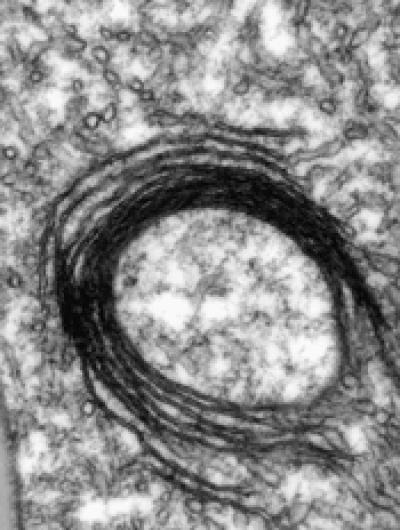

"Mice whose liver cells can't produce IRPs die of liver failure a few days after birth," says Bruno Galy, Staff Scientist in Matthias Hentze's group at EMBL, who spearheaded the work: "The mitochondria in those cells have structural defects and don't function properly, because they don't have enough iron."

Galy and colleagues found that in cells that cannot produce IRPs, the mechanisms for iron export and storage go into over-drive, while iron import is drastically reduced. This combination of factors leads to an iron shortage in the cell. As a consequence, the mitochondria don't receive enough iron, so they can't function properly, and can't make enough haem and iron sulphur clusters available to the cell machinery that depends on them. In short, the role of IRPs is to ensure that there is enough iron available in the cell to sustain mitochondrial iron needs.

This mechanism for regulating iron balance could be particularly important in cells with very high mitochondrial iron needs, such as red blood cell precursors that manufacture copious amounts of haem for oxygen transport. However, this may well be a double-edged sword. Indeed, there are situations in which mitochondria get iron but are not able to make use of it. The cell interprets this as a sign of mitochondrial iron insufficiency and responds by activating IRPs, which ultimately results in detrimental iron overloading of mitochondria. This may underlie the pathology of several diseases including inherited sideroblastic anaemias – in which cells are unable to incorporate iron into haemoglobin – or the neurodegenerative disorder Friedreich's ataxia, which the EMBL scientists are currently investigating.